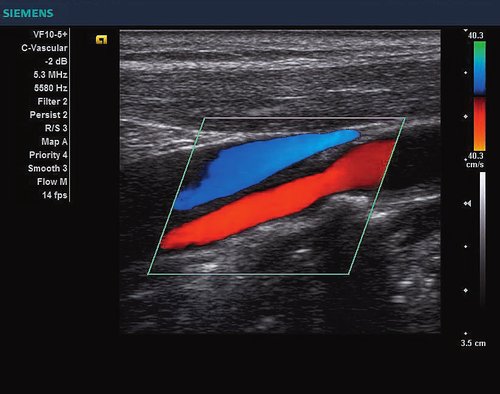

Das Siemens Acuson X300 PE ist ein mittelklassiges Herz-Kreislauf-Ultraschallgerät mit gemeinsamen Servicefunktionen. Die Premiumedition verfügt über 4D-Technologie und eine doppelte Auswahl an Sonden; zusammen mit vielen hochwertigen Funktionen ist sie in einem mittleren Preissegment erhältlich. Das Siemens ACUSON X300 PE bietet eine Vielzahl von Lösungen, einschließlich allgemeine Bildgebung, interdisziplinäre  Dienstleistungen, OB/GYN, Kardiologie, Urologie, Endokrinologie, Notfallmedizin und viele andere fachspezifische Anwendungen.

• Features: 3D, 4D, Farb/Doppler